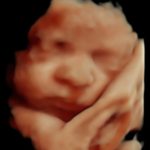

4D/5D/HD Ultrasound Gallery

Gallery